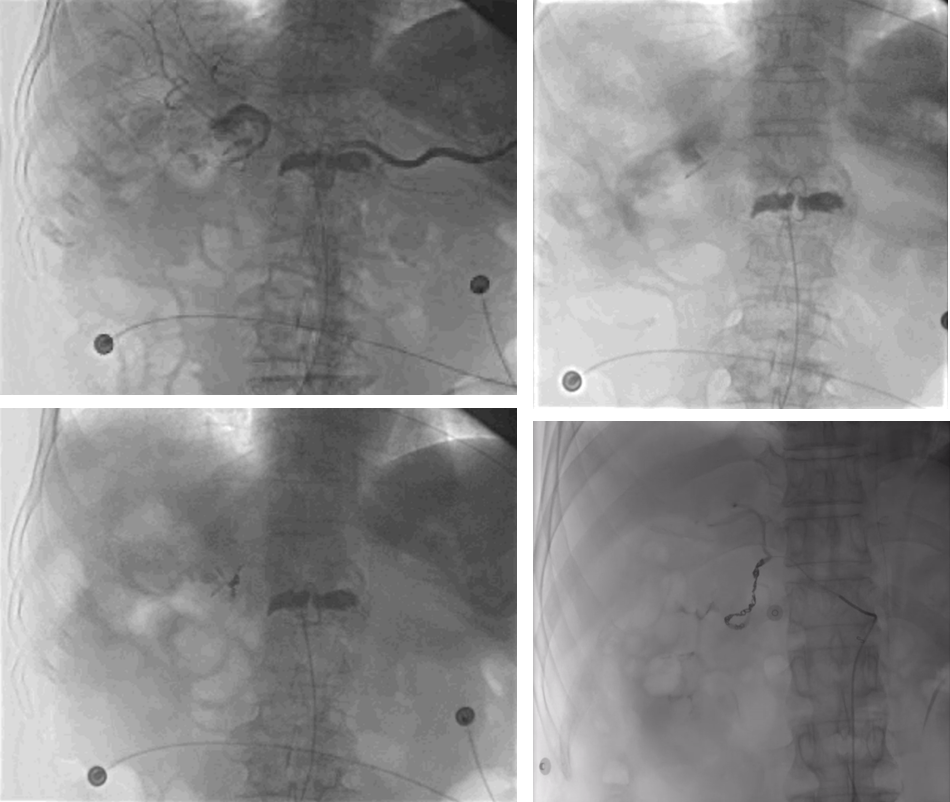

图:痔疮出血(引自苏大附二院介入科)

图:门静脉高压症

图:造影剂外溢

图:A:空肠动脉畸形;B回盲部肿瘤染色:CD:胃十二指肠动脉瘤

图:十二指肠溃疡出血,腹腔干造影,未见外渗,超选胃十二指肠动脉造影见外溢

图:A:微导管进入左结肠动脉降支,造影,未见造影剂外溢;B:经微导管注射尿激酶12万U、肝素3000U、前列地尔10μg, 20min后行激发血管造影。出现造影剂外渗。

图:增强CT造影剂外溢

图:A:动脉期十二指肠球部、降段见结节状及线状高密度影;B:静脉期十二指肠内高密度影增多,强化程度稍减低。

★ 病例1:十二指肠溃疡出血:超选造影发现外溢,弹簧圈联合微球栓塞成功止血

★ 病例2:十二指肠球部溃疡伴出血

★ 病例3:结肠出血点栓塞

图:胆囊结石、胆总管结石术后 1 个月呕血及黑便;血管造影肝右动脉假性动脉瘤

图:肝门胆管癌PTCD 、胆道支架术后 3 天,引流管反复引出血性胆汁;肝动脉造影未见异常,导丝交换撤出引流管后再次行肝动脉造影,对比剂经引流道外溢至腹腔。

图:造影见胃十二指肠动脉近段动脉瘤,并可见造影剂溢出;弹簧圈栓塞后动脉瘤闭塞。

图:胰十二指肠切除术后11天出现便血和黑便;肠系膜上动脉造影见分支动脉假性动脉瘤。